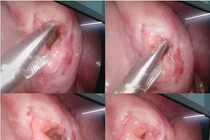

Đầu tiên, ê-kíp tiến hành nội soi niệu đạo thám sát. Qua màn hình nội soi, các bác sĩ ghi nhận vùng niệu đạo trước của bé đã bị tổn thương xơ sẹo, hẹp bít hoàn toàn khiến ống soi không thể di chuyển qua được. Trước tình trạng này, ê-kíp quyết định tạo hình lại đoạn niệu đạo trước bị chấn thương.

Quá trình mổ thám sát ghi nhận đoạn niệu đạo trước đứt rách cũ, mô xung quanh đã xơ hóa và bít tắc. Các bác sĩ đã tiến hành cắt bỏ đoạn niệu đạo xơ hẹp và khâu nối tận - tận phục hồi lại lưu thông niệu đạo. Hiện tại, bệnh nhi đang được lưu thông tiểu.